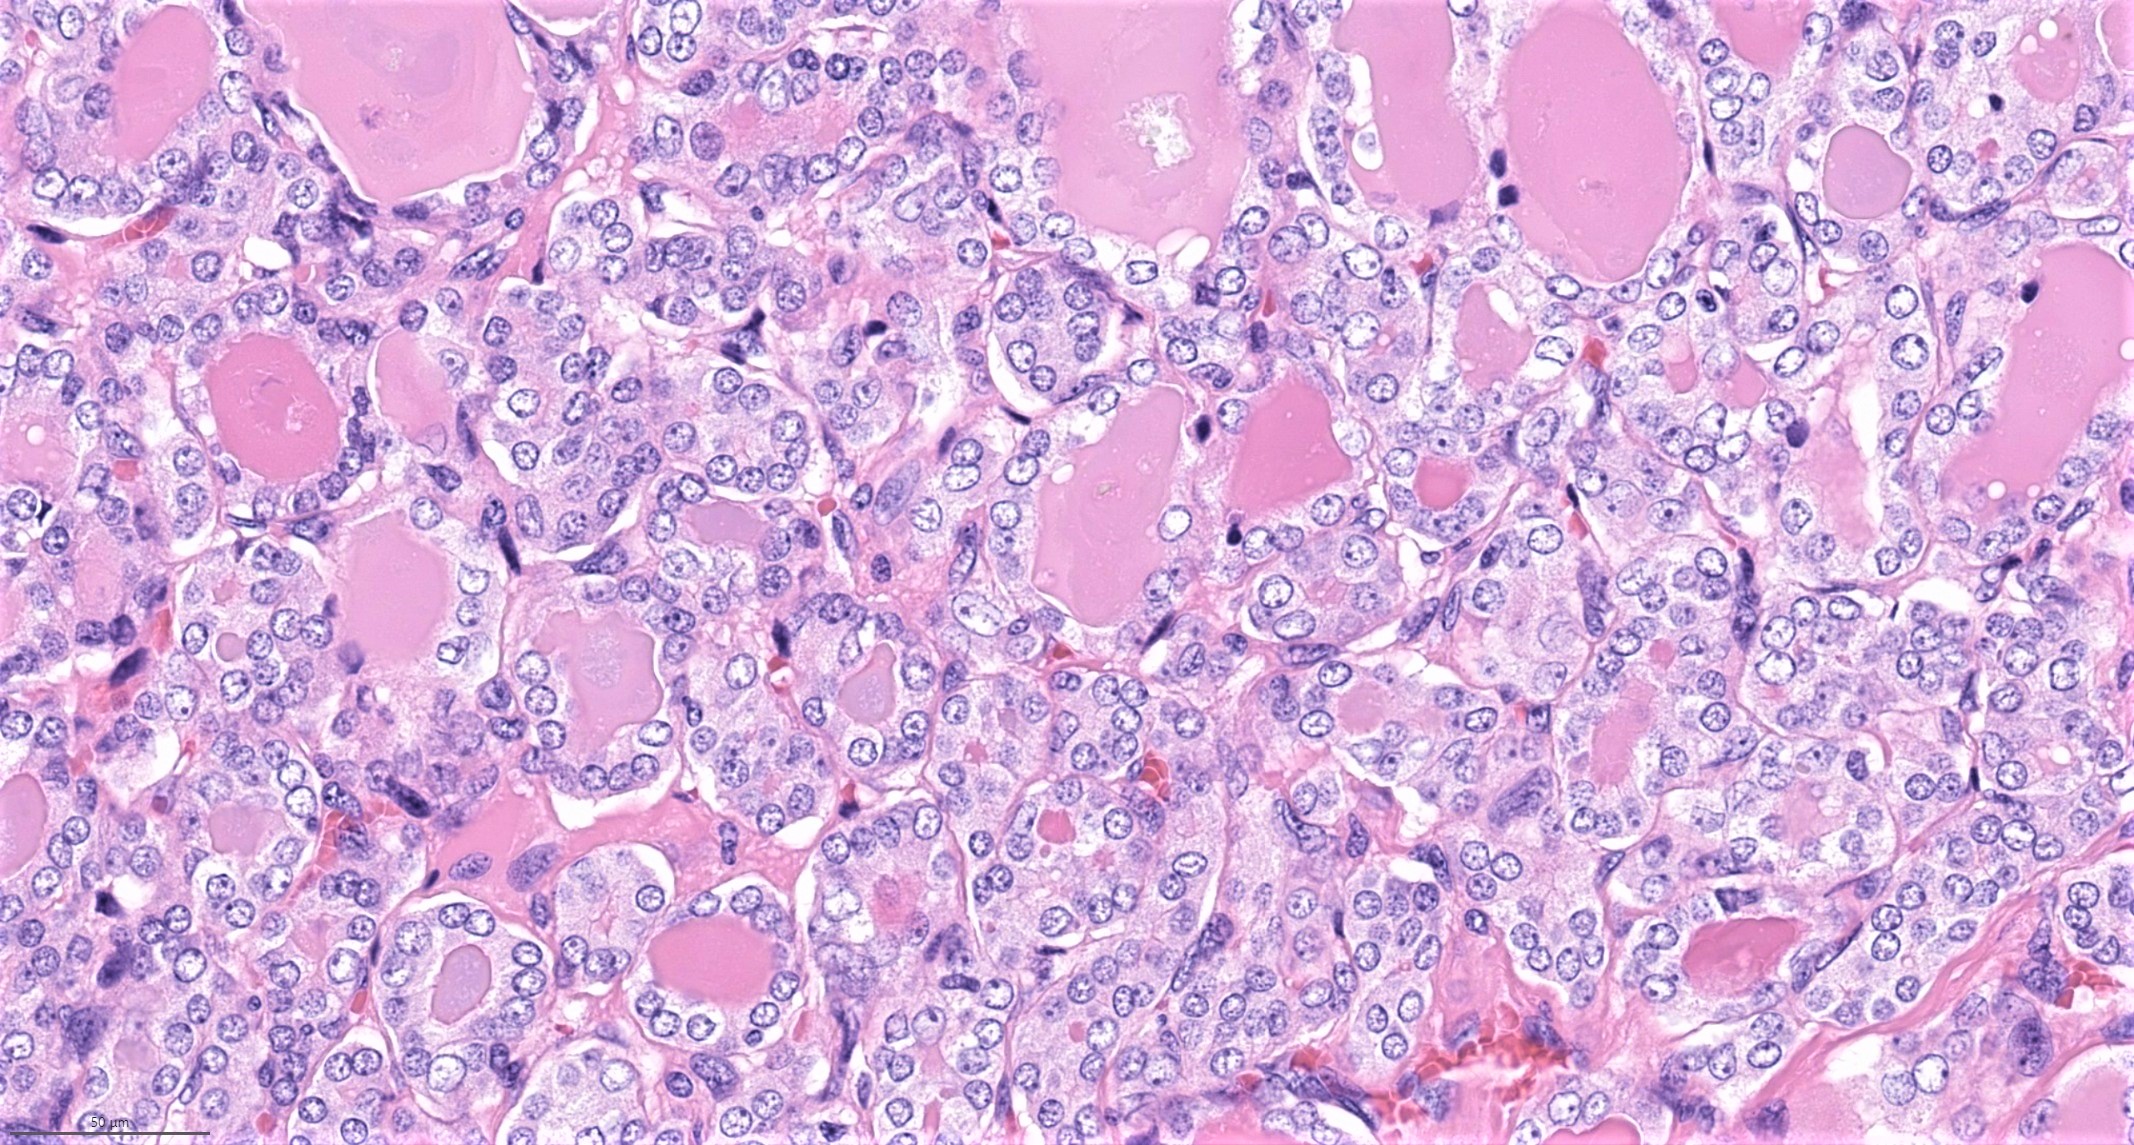

Microscopic (histologic) description

- Nuclear features of papillary thyroid carcinoma should be seen multifocally (at least 2 foci) or diffusely within the tumor; such features include nuclear enlargement, nuclear overlapping, chromatin clearing, nuclear membrane irregularity and nuclear grooves (J Clin Endocrinol Metab 2017;102:15)

- Nuclear score 2 - 3 (JAMA Oncol 2016;2:1023)

- Nuclear pseudoinclusion, a feature commonly seen in classic and tall cell variant, is rarely present in follicular variant

- Architecture: exclusively or nearly exclusively follicular

- True papillae with fibrovascular core are in general absent in follicular variant

- "Bubble gum colloid", i.e. dense homogenous hypereosinophilic colloid, may be seen in the lumen of neoplastic follicles; scalloping of colloid may be seen

Microscopic (histologic) images